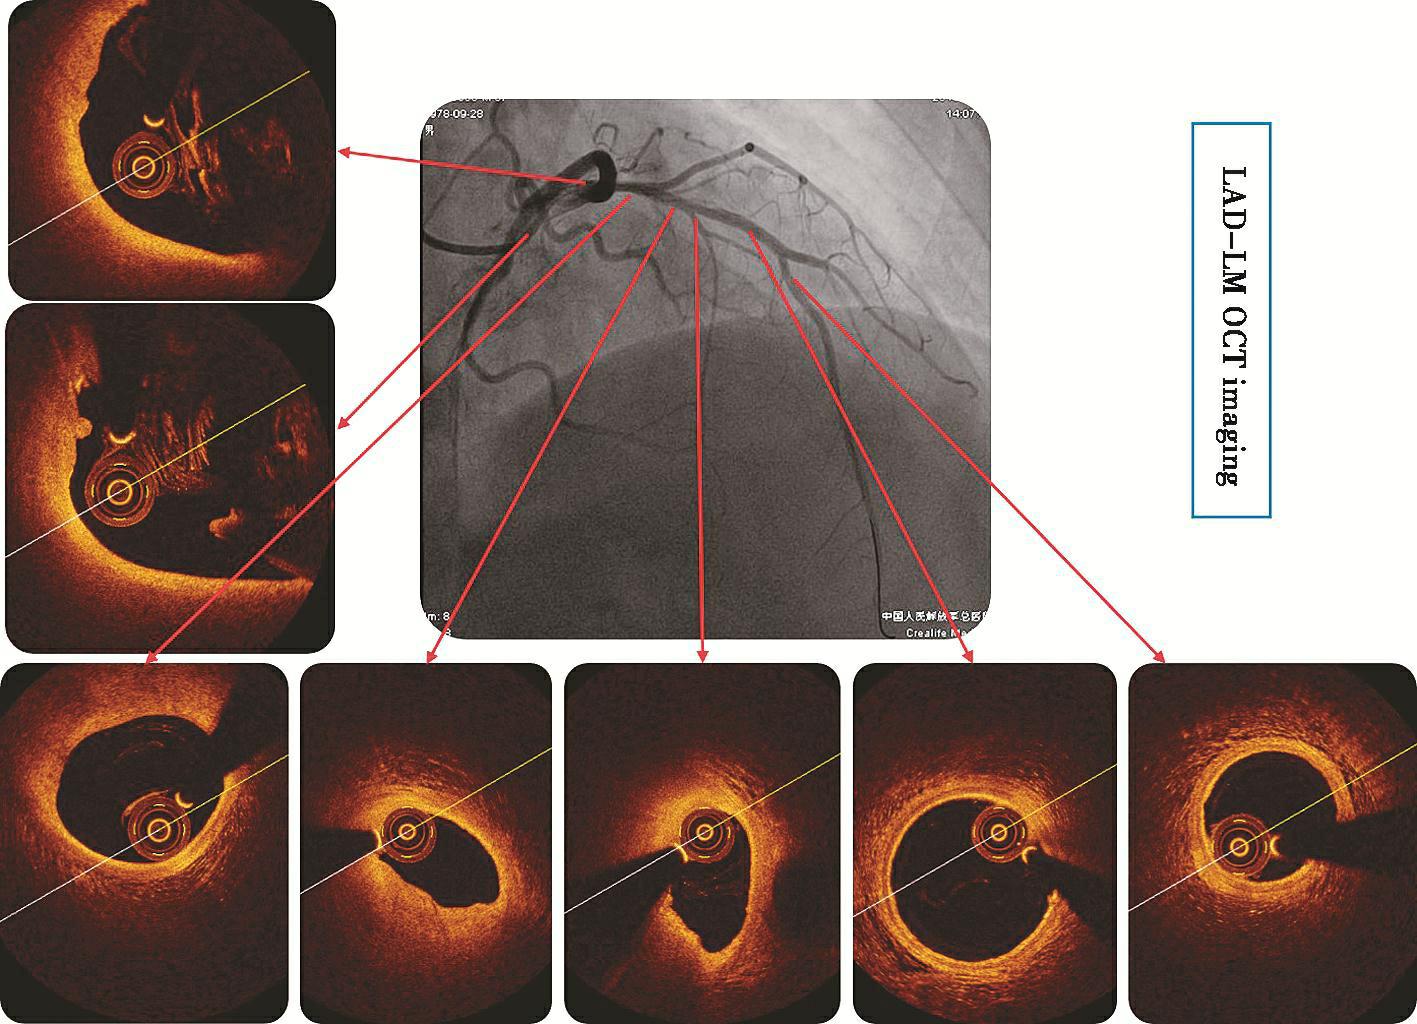

OCT(见彩图4)示:前降支远段三层结构清晰,近中段可见血栓影,最小管腔面积为2.67mm2,前降支近段及左主干内可见脂质斑块影,斑块表面侵蚀、血栓附着,未行支架植入。后完善超声右心声学造影:10ml手振生理盐水,经左上肢贵要静脉快速推入,右心房充分显影后未见微泡进入左心房,排除右向左分流的可能。

图4前降支OCT影像

前降支OCT图像前降支远段三层结构清晰,近中段可见血栓影,最小管腔面积为2.67mm2,前降支近段及左主干内可见脂质斑块影,似可见斑块表面侵蚀、血栓附着